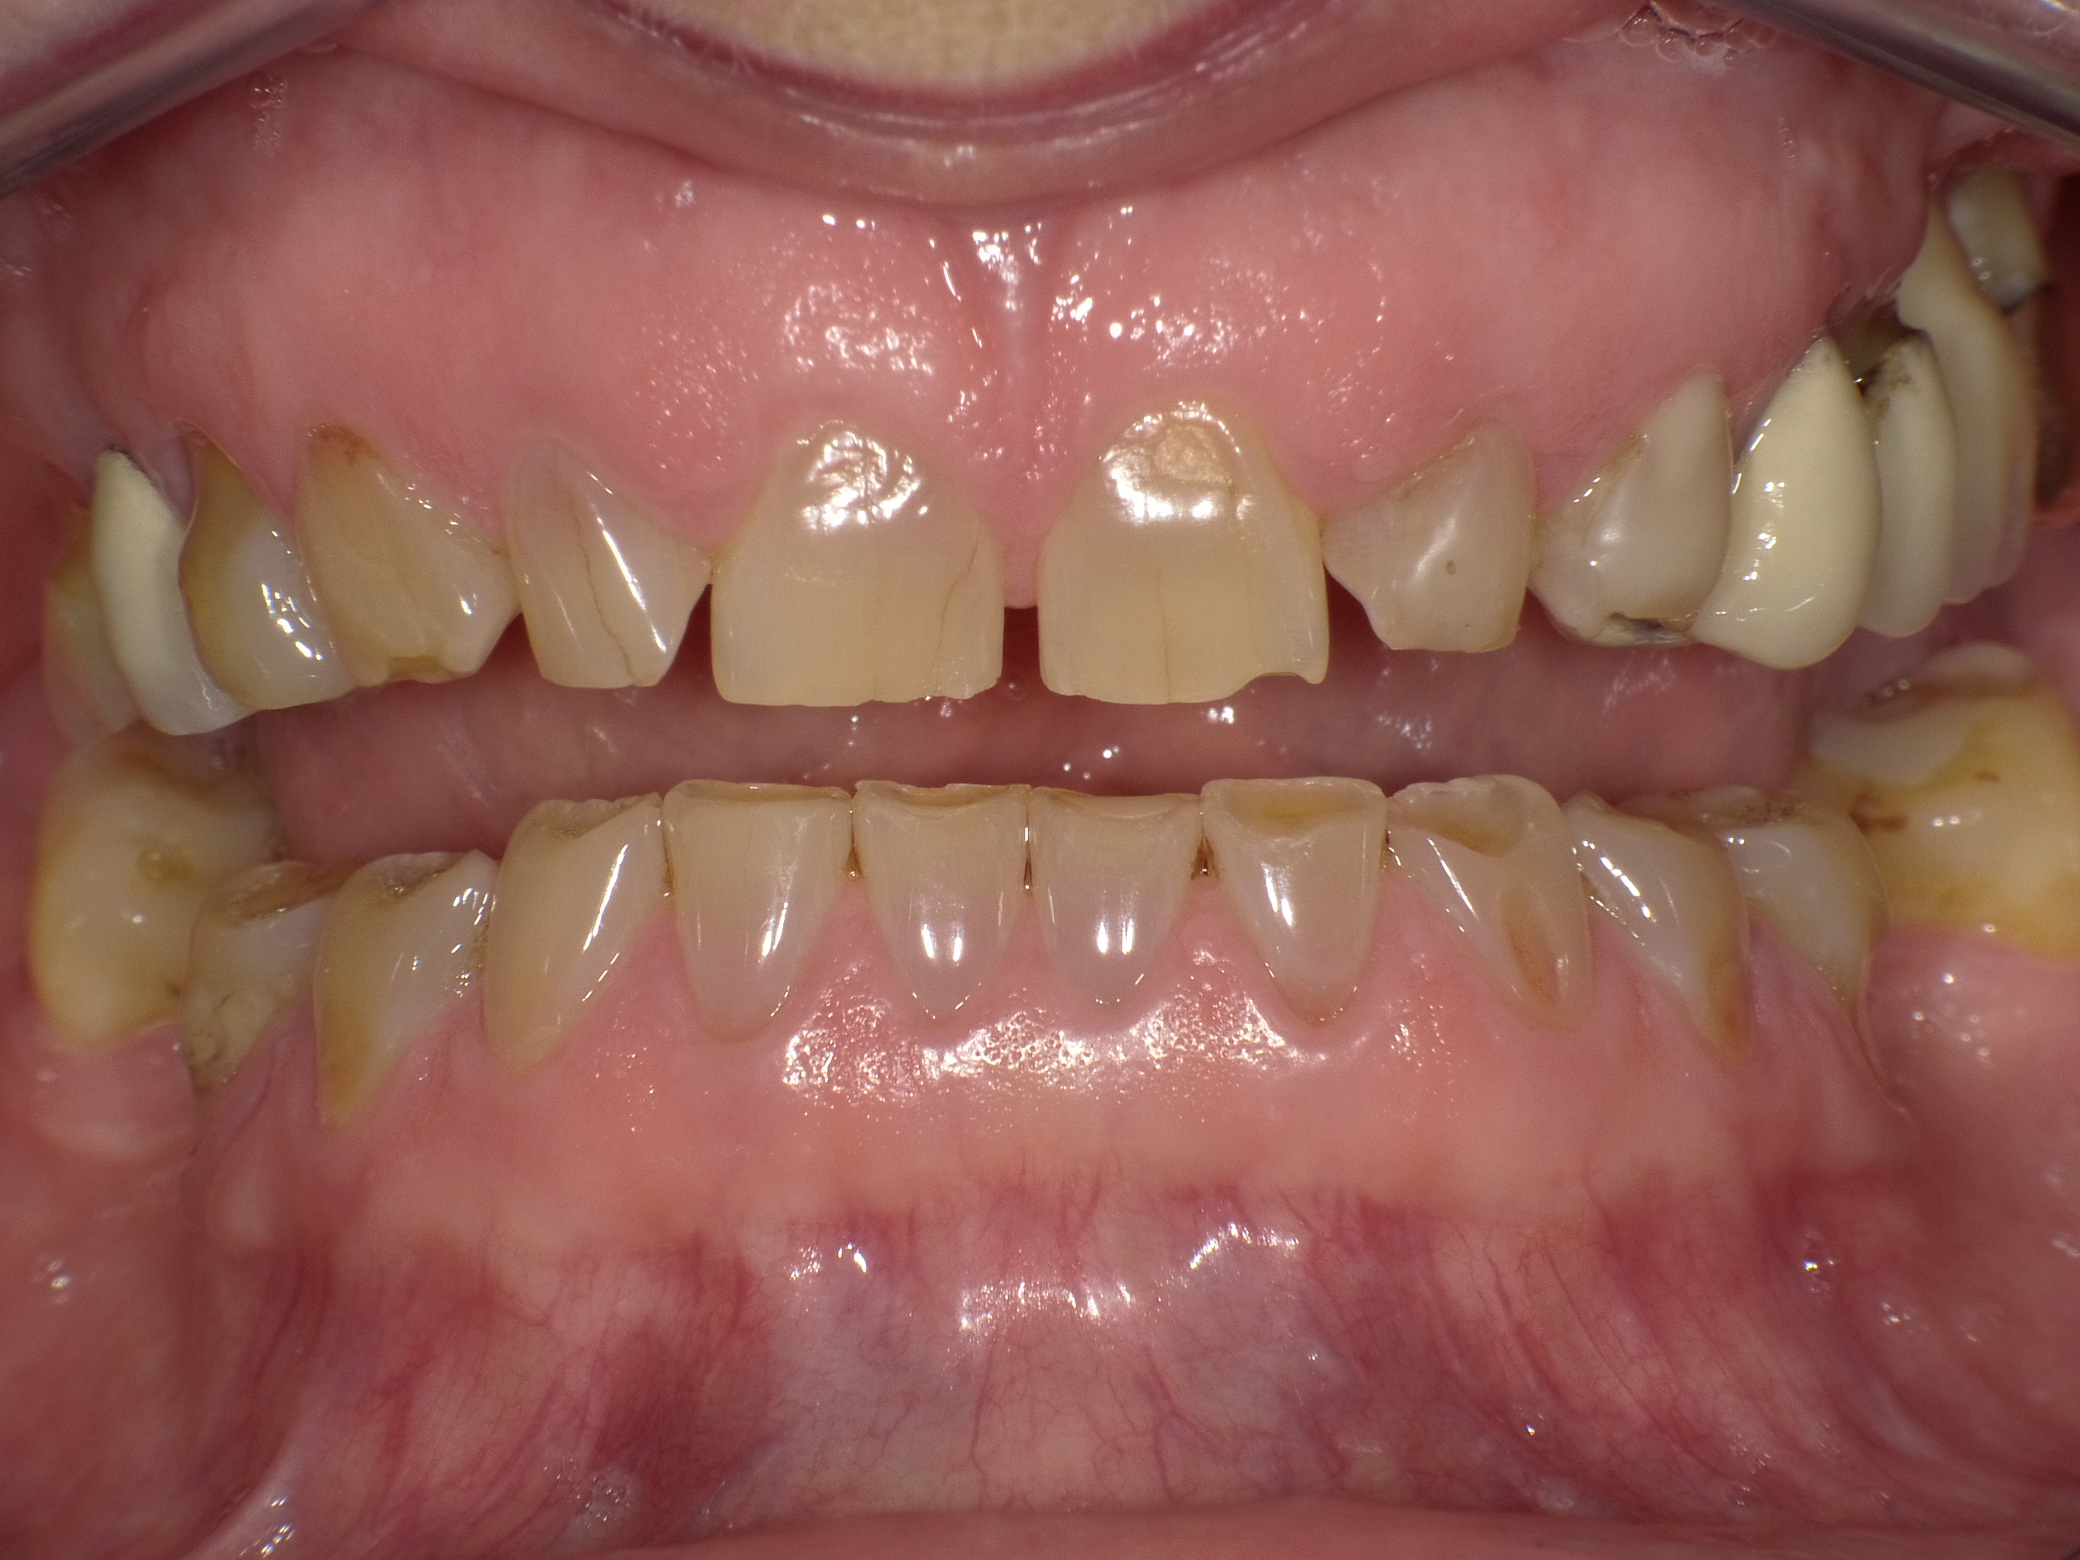

Unbefriedigende Ästhetik, vor allem aber Entzündungen im Knochen und eine massive Parodontitis mit bereits gelockerten Zähnen

Vorher: Unbefriedigende Ästhetik, vor allem aber Entzündungen im Knochen und eine massive Parodontitis mit bereits gelockerten Zähnen

Gesamtbehandlung in Sedierung: die Seitenzähne wurden durch Keramik-Implantate (Zahnentfernungen und Sofortimplantation) mit Knochenaufbau ersetzt; anschließend Gesamtüberkronung aus Vollkeramik mit Optimierung der Ästhetik

Nachher: Gesamtbehandlung in Sedierung: die Seitenzähne wurden durch Keramik-Implantate (Zahnentfernungen und Sofortimplantation) mit Knochenaufbau ersetzt; anschließend Gesamtüberkronung aus Vollkeramik mit Optimierung der Ästhetik